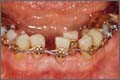

¹ÏÀ¸½Ã°Ú½À´Ï±î? ¿ìÃø ÁßÀýÄ¡ ÀÚ¸®ÀÇ Ä¡¾Æ´Â autotransplantationÀ» ÅëÇØ ÀÚ°¡ÀÌ½ÄµÈ ¼Ò±¸Ä¡°¡ Dr. Zachrisson¿¡ ÀÇÇØ touchµÈ °ÍÀÔ´Ï´Ù.    more